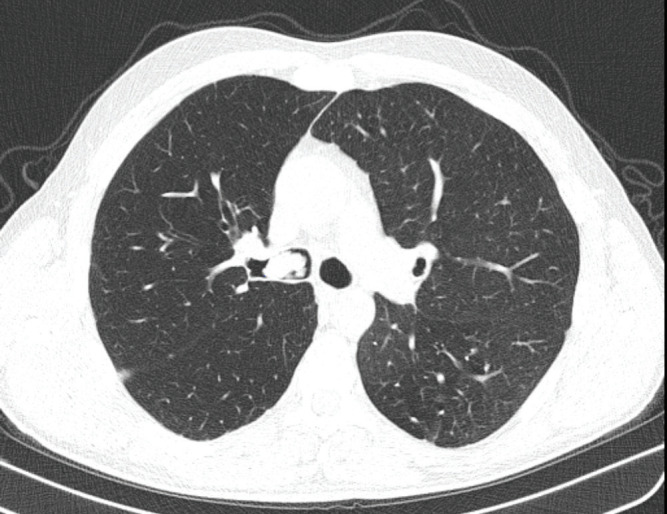

Endobronchial solitary papillomas are extremely rare lung neoplasms originating from the bronchial surface epithelium. They often present with cough or recurrent hemoptysis. These tumors are benign, but they should be followed closely because they may even have a low probability of malignant transformation features. It should be kept in mind that malignancy may develop especially if the patient is a smoker. Although the etiology is not known for certain, it is thought to be caused by human papillomavirus in some cases. A 43-year-old male patient was admitted with a complaint of chronic cough. Rigid bronchoscopy was performed for diagnostic and therapeutic purposes after imaging techniques revealed a lesion obstructing the lumen of the right main bronchus. The pathology result was reported as mixed bronchial papilloma. We aimed to present our case because of its rarity and to indicate that chronic cough must be further evaluated.

Abstract Image